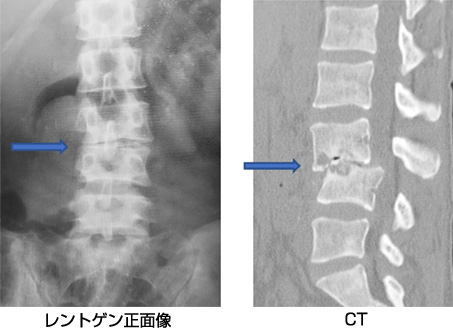

脊髄・脊椎疾患 | 名古屋大学大学院医学系研究科 脳神経外科学, 頚椎脊柱管狭窄症の症例と症状について|白石脊椎クリニック,

脊椎脊髄センター | 総合東京病院【公式】中野区 練馬区 24時間, 腰椎変性疾患 | 総合東京病院【公式】中野区 練馬区 24時間救急受入,

腰椎変性疾患 | 総合東京病院【公式】中野区 練馬区 24時間救急受入, 脊椎脊髄疾患について・主な疾患 | 一般社団法人 日本脊椎脊髄病,